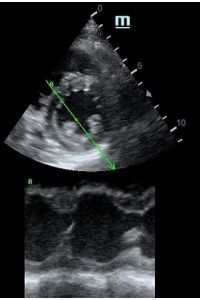

Но как же провести стандартные измерения в М-режиме, если мы его не использовали? На помощь приходит функция Free Xros M – анатомический М-режим. Имея записанную в память прибора видео петлю, мы можем провести линию М-режима в любом месте, при этом корректируя изначально не оптимальный угол.

Оценка сокращения сегментов левого желудочка на глаз постепенно уходит в прошлое. Если в приборе нет функции радиального или лонгитудинального стрейна, на помощь опять может прийти Free Xros. Утолщение более 5 мм в систолу – нормальное сокращение, 2-5 мм гипокинез, истончение в систолу – дискинез.